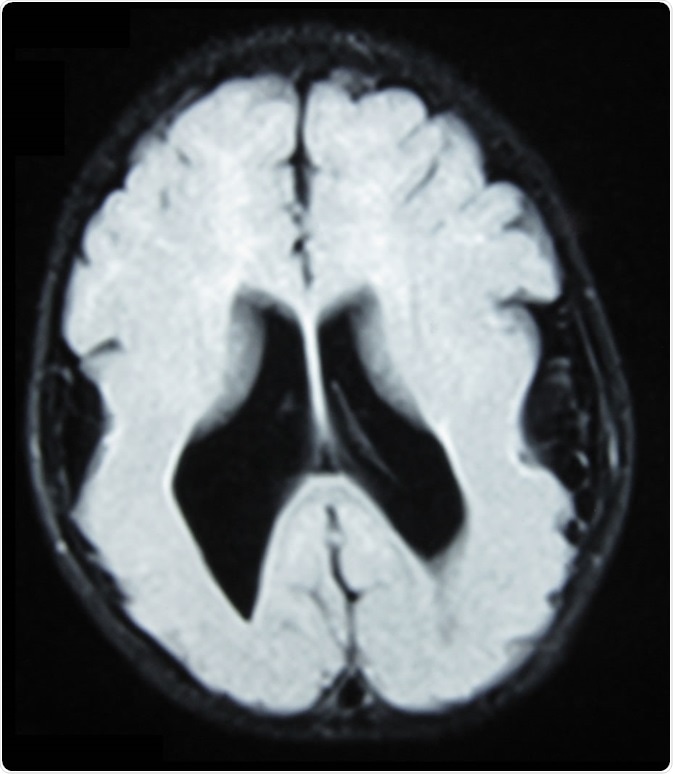

Brain MRI, T1 weighted, transverse plane, that shows lyssencephaly, manifested as scarce and wide circumvolutions, mostly in the occipital, parietal and temporal lobes. As aggregated findings, there is ventriculomegaly, no true Sylvian cissure, too thick gray matter and ectopic gray matter in the white matter. Image Credit: Ralphelg, https://creativecommons.org/licenses/by-sa/3.0/deed.en